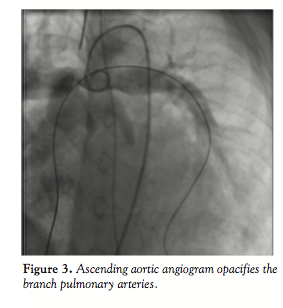

further delineate the anatomy. Ascending aortic angiogram showed significant opacification of the PAs (Figure 3). The aortopulmonary window could be crossed easily from the PA into the aorta by advancing a wedge catheter with the balloon inflated; hence, its diameter was above 1 cm. It was decided not to balloon-size the defect, because of the possibility of further increasing its size. Therefore, a 34-mm long covered stent that was premounted on a 16-mm diameter balloon was chosen and implanted at the exact point of the window, sealing it off and at the same time relieving the left PA stenosis (Figures 4 and 5).